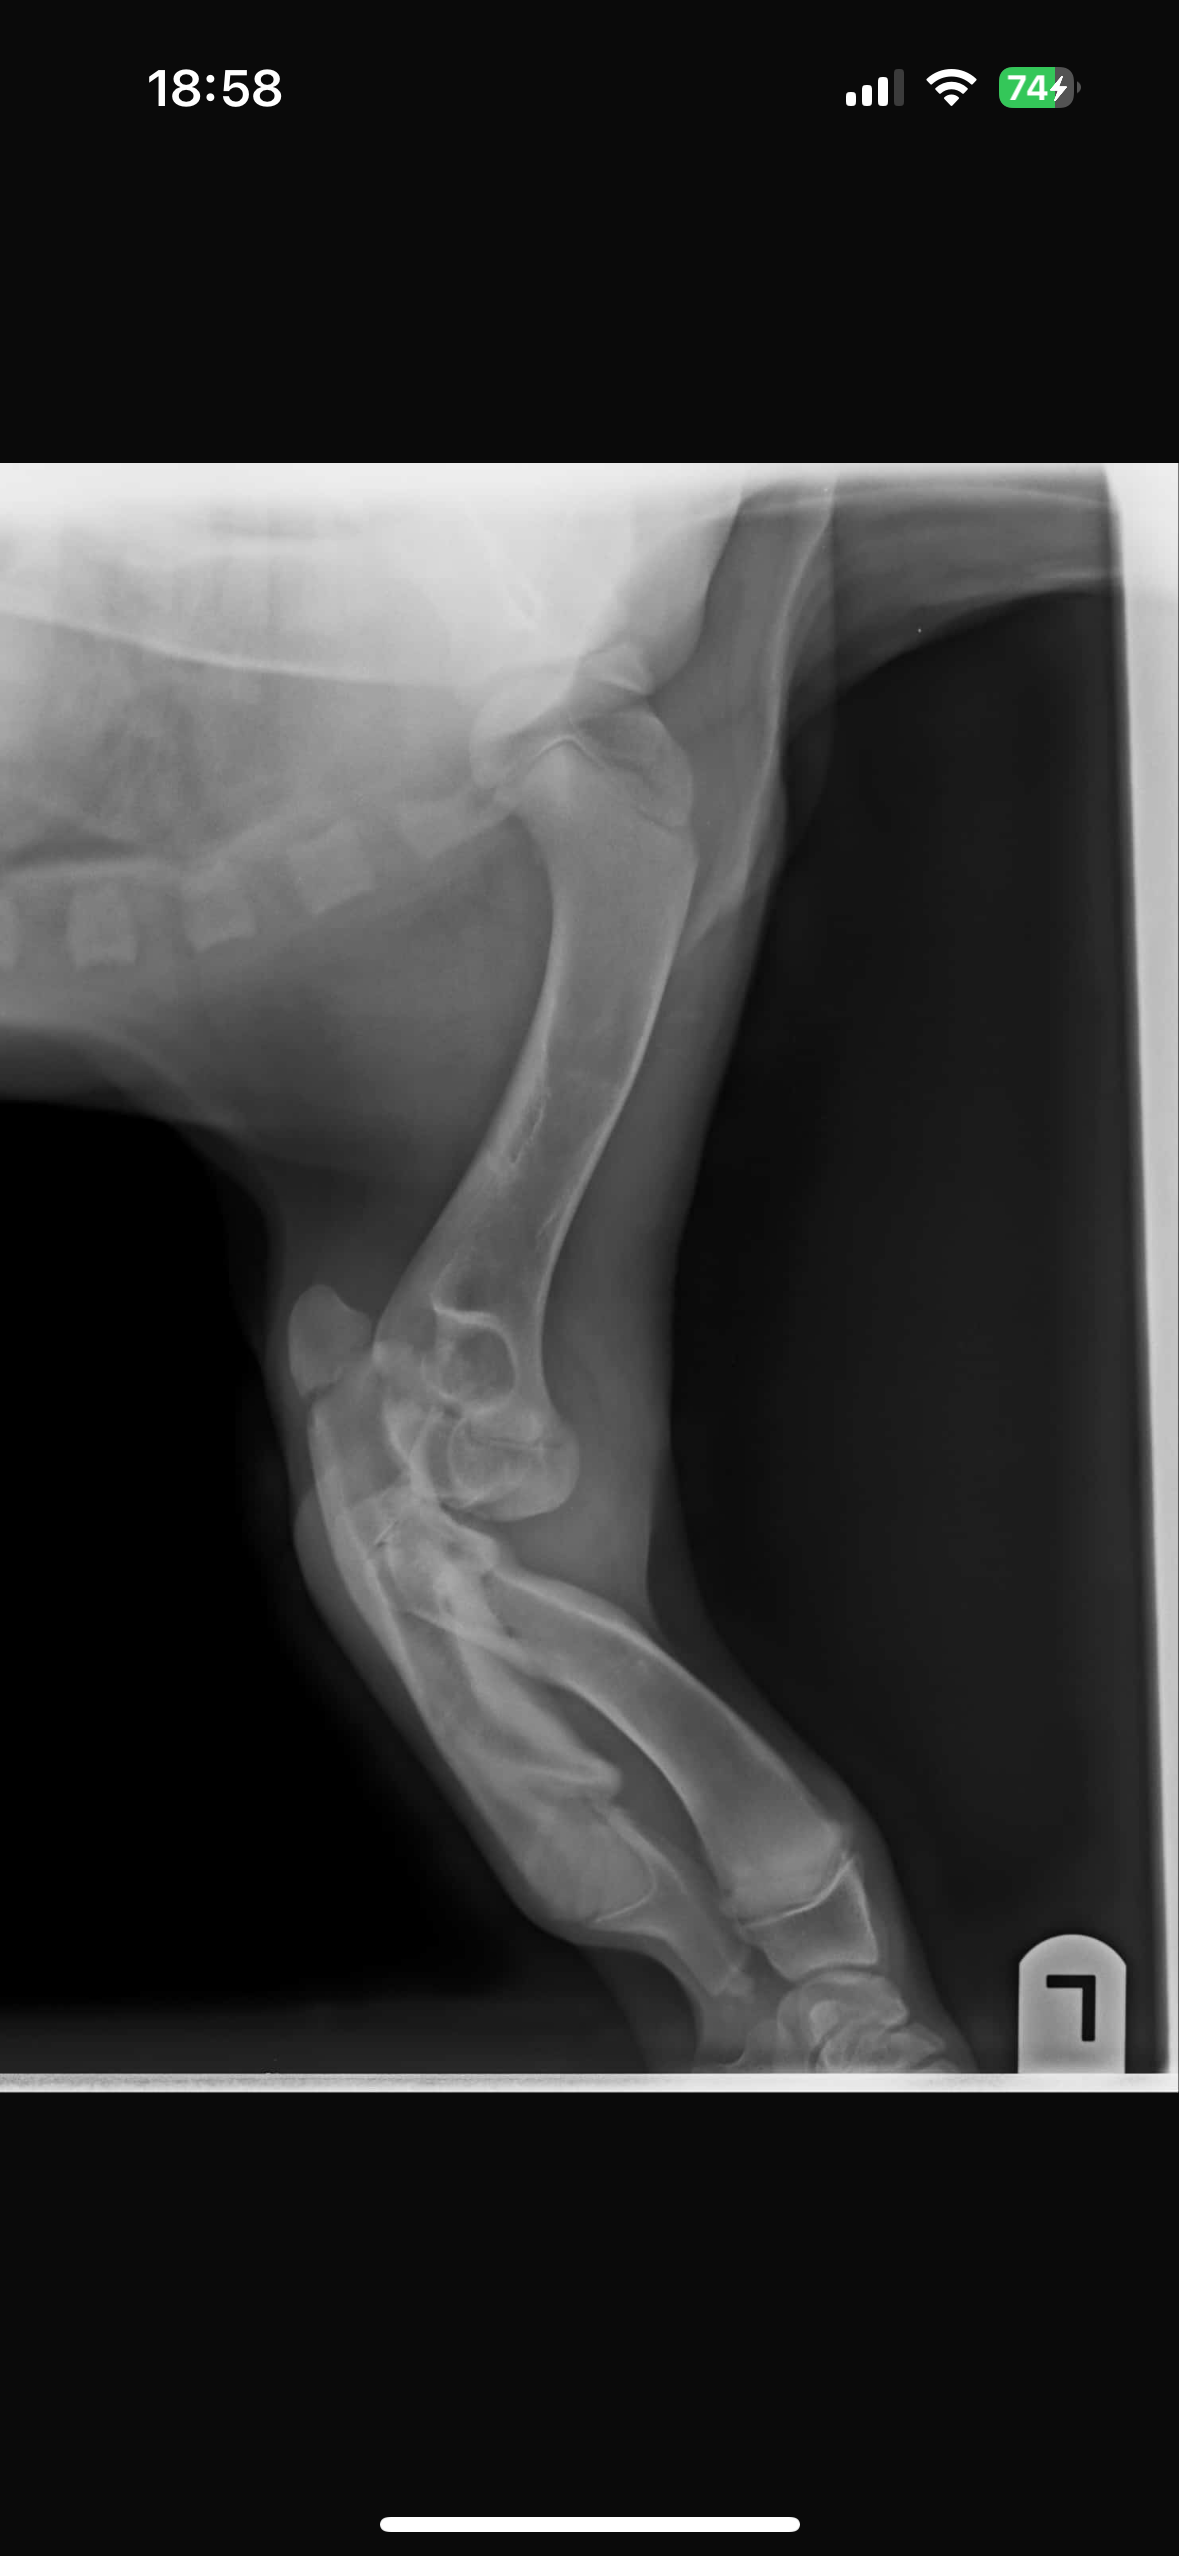

ABER leider wurde Mogli mit einer schweren Fehlbildung an beiden Vorderbeinen geboren. Jeder Schritt bedeutet für ihn Schmerz und ohne eine Operation wird Mogli niemals richtig laufen können.

Mit einer speziellen Operation besteht die Chance, dass Mogli endlich ein schmerzfreies, glückliches Leben führen.

Die Operation wird vom Spezialisten Dr. Tack durchgeführt.